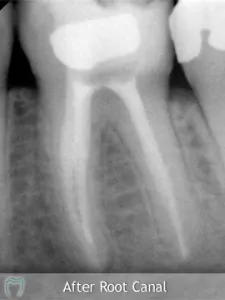

Treatment at our clinic is offered on a private basis and also to PRSI-qualified patients. Services include all routine dental treatment (examinations, cleanings, fillings etc.), cosmetic dentistry such as teeth whitening, bonding and porcelain veneers as well as more advanced procedures including the provision of crowns and bridges and dental implants.

Listed below are some of the treatments and services we offer. We’ve also included several real life ‘case studies’ which demonstrate what can be encountered, and how we’ve managed the case.